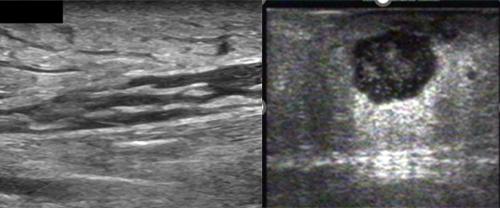

Abscess

On ultrasound, abscesses appear as spherical or oblong collections of fluid that are anechoic or hypoechoic, and may contain hyperechoic debris. Motion of the abscess cavity contents may be elicited with gentle probe pressure (Swirl Sign). The fluid can be uniform throughout, or it may have areas with internal echoes that make it heterogeneous. In addition posterior acoustic enhancement may be present.

Example A

Example B

Abscess contents may on occasion appear isoechoic with surrounding tissue. Slight probe pressure will elicit the “swirl sign” to improve diagnostic accuracy.